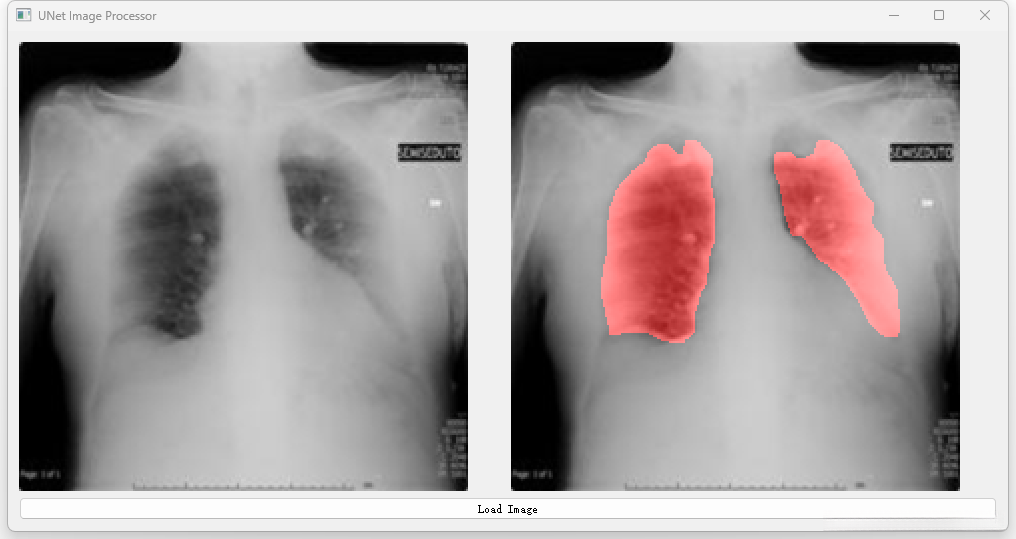

开发一种高效且可靠的U-Net网络架构以解决肺部CT图像分割任务。 通过优化算法设计提升图像分割精度的同时有效抑制噪声污染和伪影生成。 实现对肺部各区域(如支气管血管网等)的精细解析确保诊断准确性。 设计一个操作便捷的人机交互界面便于临床医师进行影像分析及评估。

将经过优化的Unet架构应用于实际临床CT扫描数据中进行分割操作,并实现精准识别目标区域边界的目标达成。

对分割结果实施后端质量控制流程:包括噪声去除、空洞填充等步骤确保最终输出满足临床应用需求的标准要求并提高准确性水平。

深度学习之基于Unet肺部CT图像分割项目

三、系统